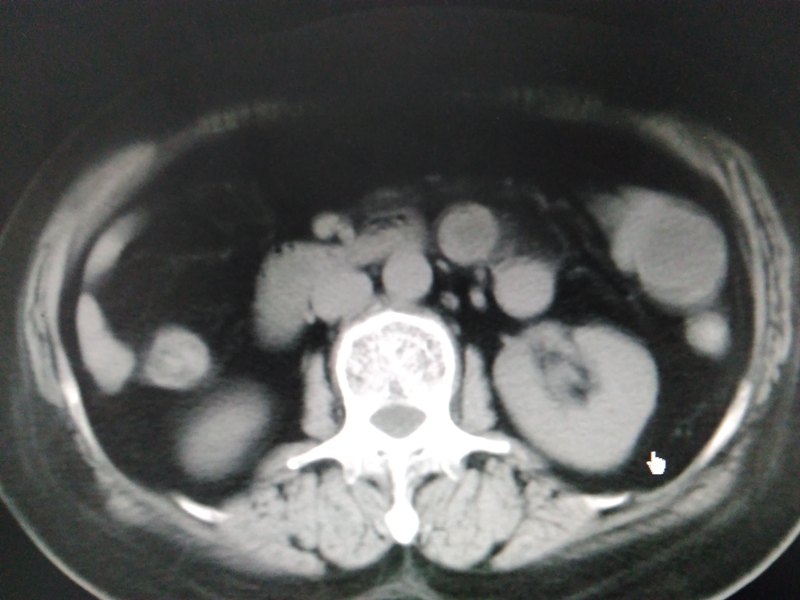

急性结肠憩室炎是一种常见疾病,结肠憩室好发于回盲部、升结肠和乙状结肠,也可分布全结肠,憩室可单发,多数为多发。临床上急性结肠憩室炎可在急诊抗炎补液后缓解,腹痛症状明显或伴有发热者需住院治疗,一般于禁食加强抗炎支持治疗后症状可缓解。大多数急性结肠憩室炎为急性蜂窝织炎,表现为结肠和系膜及其周围脂肪垂的炎症,病情进展可化脓坏疽穿孔,特别是憩室内伴有粪石,憩室根部较小者更易穿孔。结肠内容物有微小渗漏则有腹膜炎表现,大网膜多能覆盖病灶区,炎症局限,大多数保守治疗可免于急诊手术。当结肠憩室穿孔后就形成粪水性腹膜炎,需要及时急诊手术治疗,本病例部位在回盲部,CT复查回盲部憩室炎伴穿孔,阑尾已增粗考虑继发性阑尾炎,因此行腹腔镜下憩室切除+阑尾切除术,手术顺利。 总之,结肠穿孔破裂,排除肿瘤、异物刺伤和外伤,多数为急性结肠憩室炎所致。 结肠憩室炎只有大出血、穿孔、梗阻或脓肿形成等情况下,需急诊手术治疗。腹腔镜手术是其首选手术方式,对于憩室较大的可用内镜切割闭合器切除憩室,小憩室穿孔可直接套扎器套扎即可,也可全层倒刺线缝合。对于结肠炎症严重水肿明显,全层倒刺线缝合更安全,再将大网膜缝在边缘覆盖穿孔区,旁边放置引流,考虑肠漏可能大者放置冲洗引流双套管。